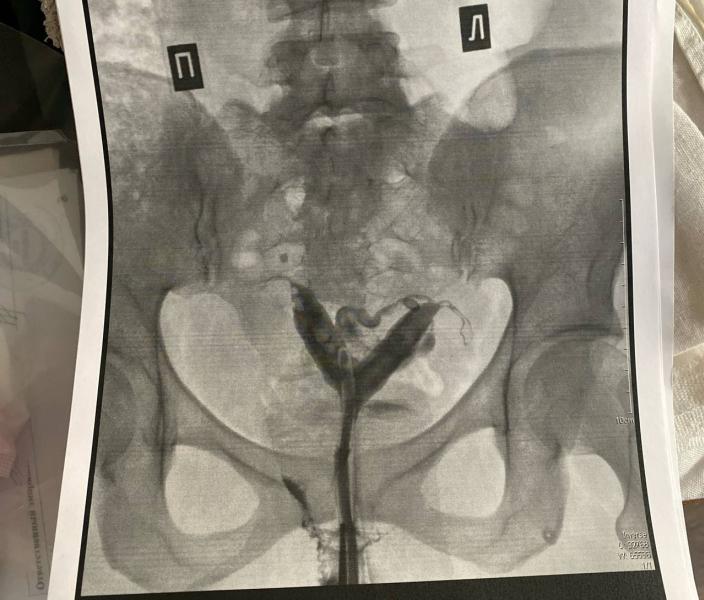

Сегодня врач сказал, что возможна операция по удалению перегородки в матке (сначала говорили что матка двурогая, теперь перегородка, приложу фото, а то я запуталась)

У меня тоже двурогая матка, перегородка доходит до средней трети цервикального канала (то есть больше, чем на половину шейки, если простыми словами). Тоже хотела сделать операцию до того, как вообще начала задумываться о детях, но она не нужна оказалась (не мне лично, а вообще в таких случаях). Нужно консультироваться именно с оперирующими хирургами, все гинекологи, с которыми я общалась на эту тему, особо не знают, что с этим делать.

Это узи или МРТ у вас?